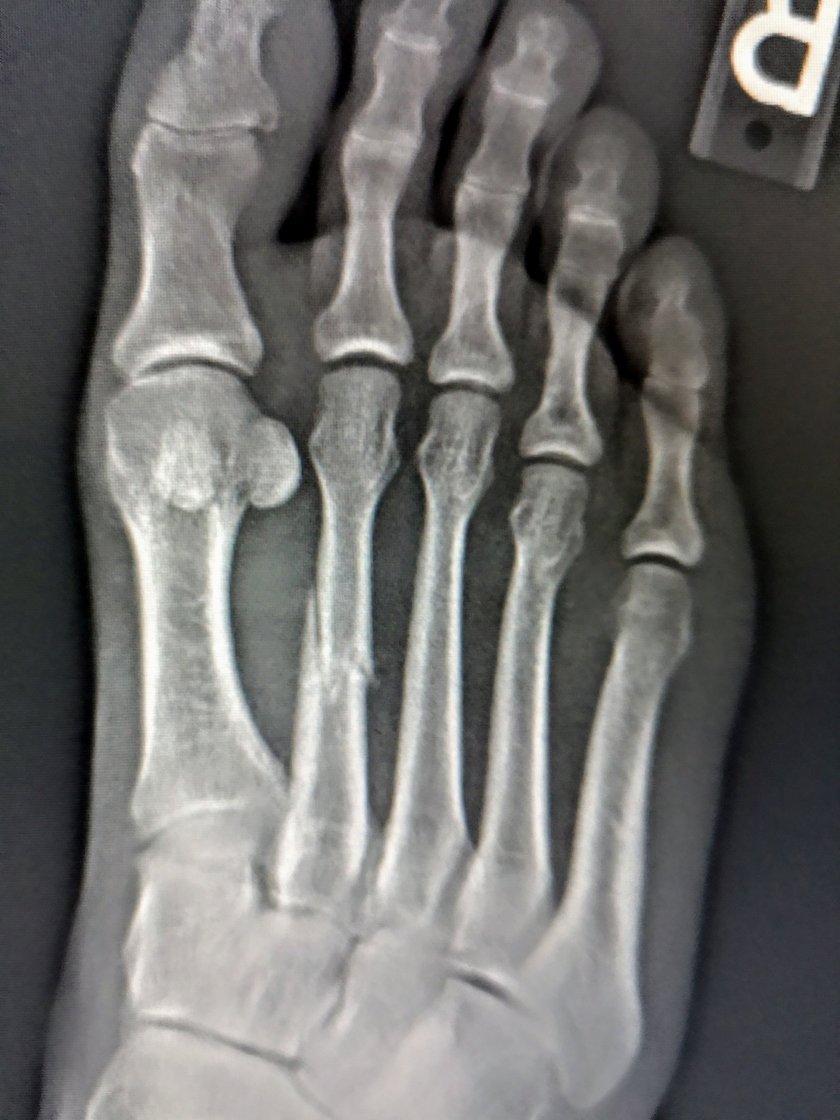

Da mein Fuss seit letztem Donnerstag nicht mehr wirklich besser wurde, hab ich mich entschlossen einen Arzt aufzusuchen. Nach 2 Std Bürokrieg, hat mir die Ärztin nach kurzer Untersuchung beschieden, es müsse ein Röngenbild her. Ich konnte dann am nächsten Morgen um 8.00 zum Röntgen. Nach kurzem Blick auf die Bilder, zusammen mit der Ärztin, konnte ich die Diagnose auch selber stellen:

Gebrochener Mittelfuess Knochen am 2. Zehen von links. 6 Wochen Stützschiene.